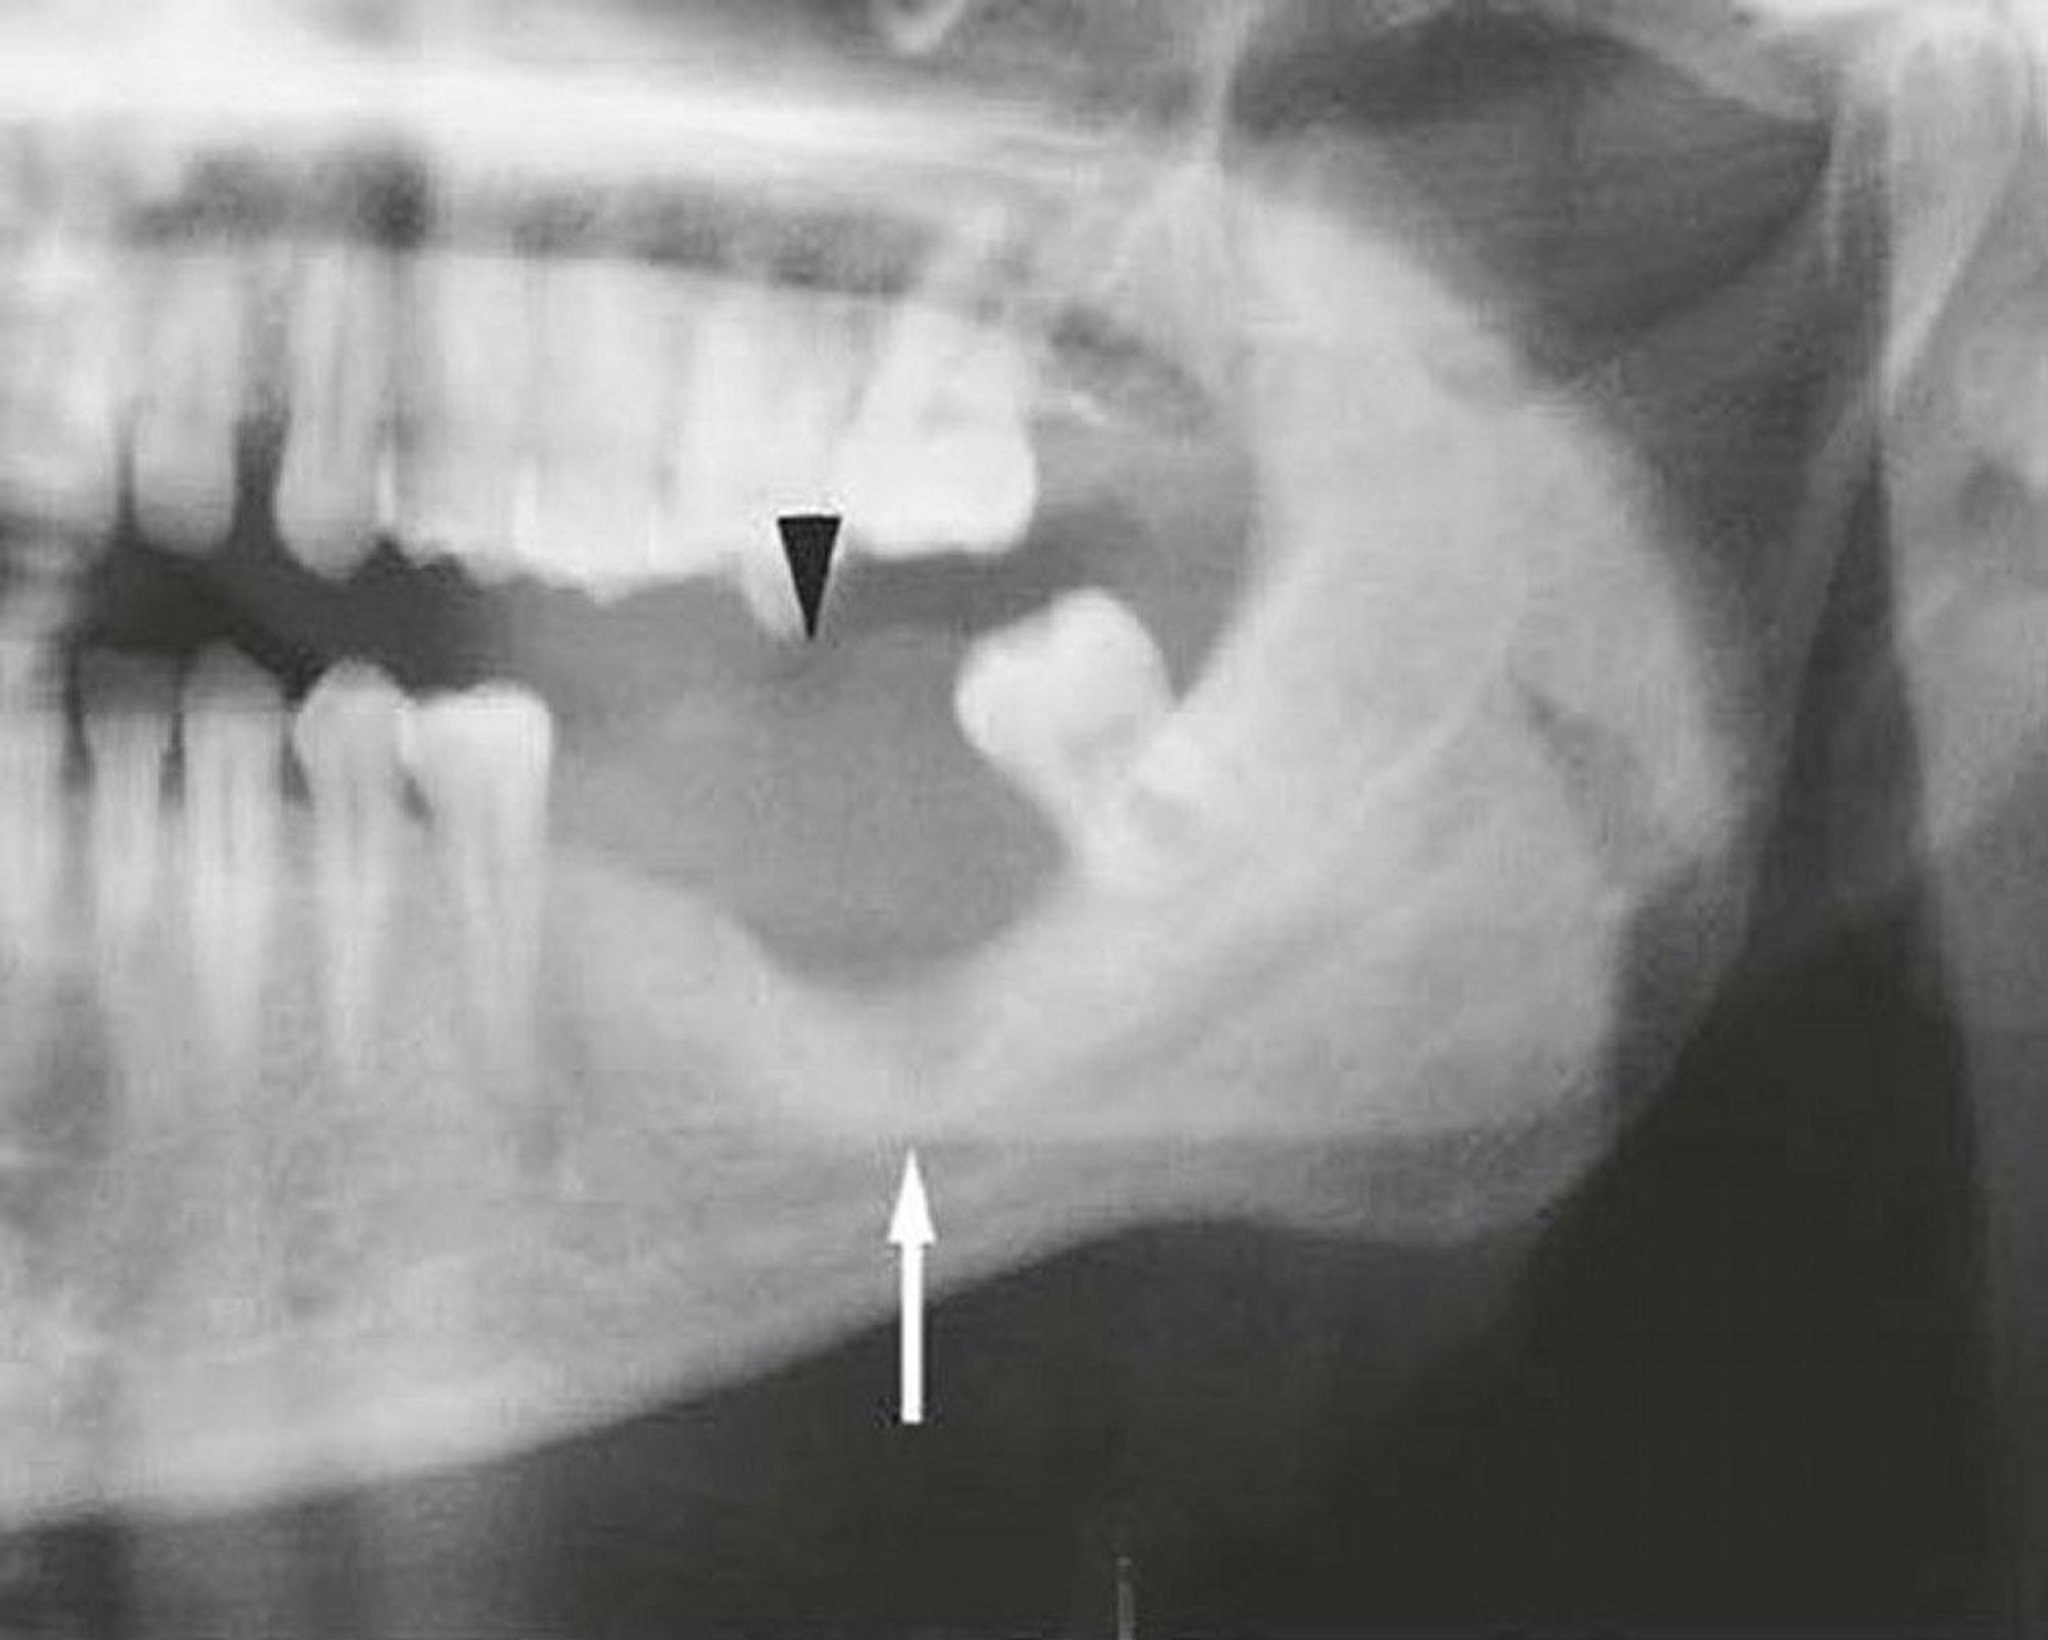

This image of a mandible invaded by squamous cell carcinoma shows a soft tissue mass (arrowhead) and bone destruction (arrow).